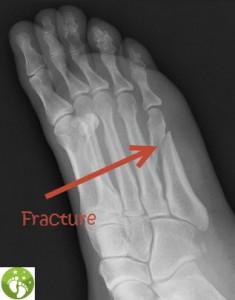

This person dropped a 60 pound kettlebell on their foot. As they tried to lift their foot, they tumbled sideways and heard a loud crack. What type of injury is this?

Question 50

The following shows....

Oblique Fractue

Greenstick Fracture

Comminuted Fracture

Fissure

Transverse Fracture

A sprain caused by a torn ligament